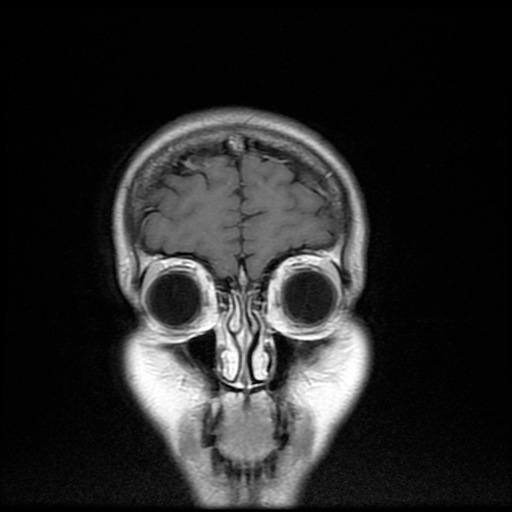

“A cat scan is different. A cat scan uses X-rays to produce cross-sectional images of the inside of your body, while the MRI uses a magnetic field and radio waves to produce these images. Both of these technologies revolutionized the medical industry when they were introduced in the ‘70’s. Before that, the only way you knew what was going on inside of your body was if they cut you open.”

“Well, I don’t know if it’s a portal,” Lyndon said, “but it’s sure cramped in there. Some people liken it to a coffin. It’s very constricting. It doesn’t bother me but, if you’re claustrophobic, you’re not going to like it.”